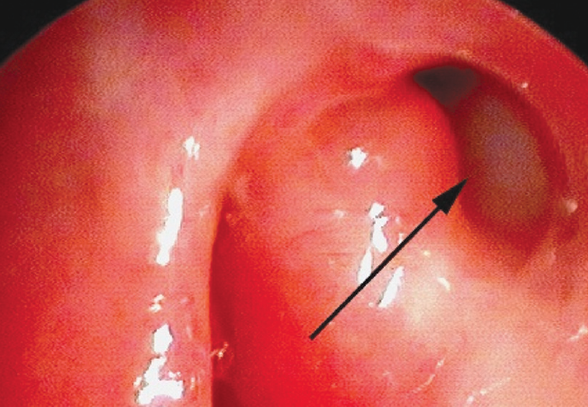

Fig. 7. Endoscopic view of a dacryocystorhinostomy-ostium (left nasal cavity) 6 months after endonasal balloon dacryoplasty; arrow indicates the lumen of the dacryocystorhinostomy-ostium

Рис. 7. Эндоскопическая картина области дакриостомы (левая половина носа) через 6 мес. после эндоназальной баллонной дакриопластики; стрелкой указан просвет дакриостомы

The following results were obtained. “Recovery” was noted in four patients and “improvement” in one, and the dacryostomy cicatrized in one patient. Figure 7 shows the endoscopic presentation of the nasal cavity 6 months after endonasal balloon plasty of dacryostomy.